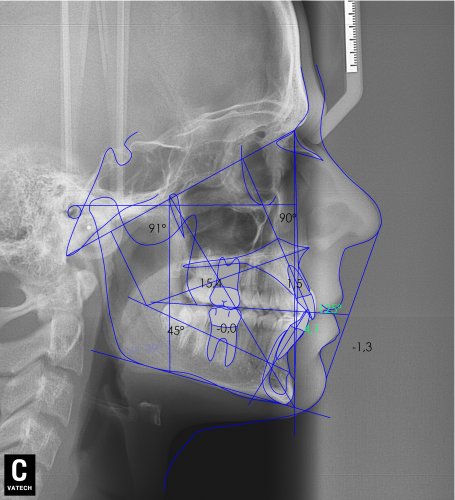

Paciente de 14 años, acude a nuestra consulta por dientes superiores proclinados hacia delante y apiñamiento. El paciente presenta una full clase 2, sobremordida y dientes inferiores proclinados. Decidimos colocarle brackets Damon y microtornillos en maxilar superior para distalizar las muelas. La duración del tratamiento fue de  24meses, y ahora lleva 1 año de contención. El paciente se pone la férula Essix superior 1noche/2 y la de abajo 1noche/semana para mantener.

MAYO 2014-RICKETTS-Lateral Xray

Image 4 De 4